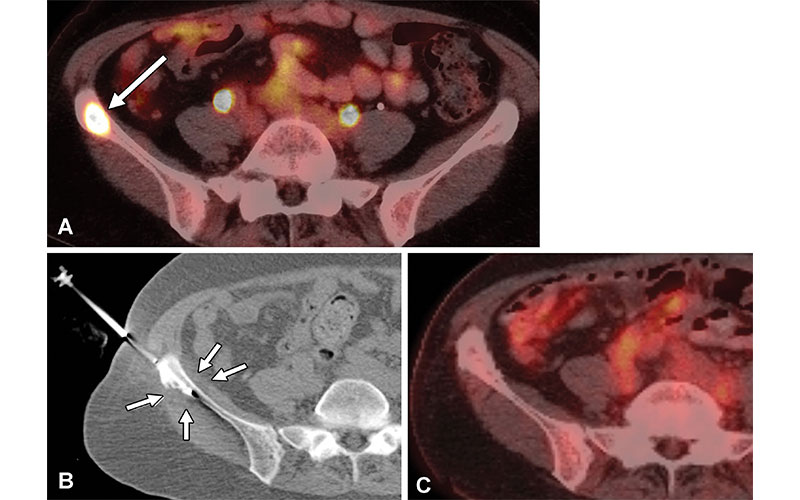

Tumor control in a 61-year-old woman with triple-positive metastatic breast cancer and a painful right iliac metastatic lesion. Cryoablation was performed for pain palliation and local tumor control. (A) Axial fluorine 18 (18F) fluorodeoxyglucose (FDG) PET/CT image shows a hypermetabolic right iliac metastatic lesion (arrow). (B) Supine axial CT image obtained during cryoablation shows placement of a cryoprobe (a total of two cryoprobes were placed) in the metastatic lesion with a hypoattenuating ice ball (arrows) encompassing the neoplastic tissue and extending to the adjacent soft tissues to ensure local tumor control. (C) Axial 18F-FDG PET/CT image obtained 3 years after cryoablation shows local tumor control and no evidence of tumor recurrence. https://doi.org/10.1148/rg.220009 © RSNA 2022